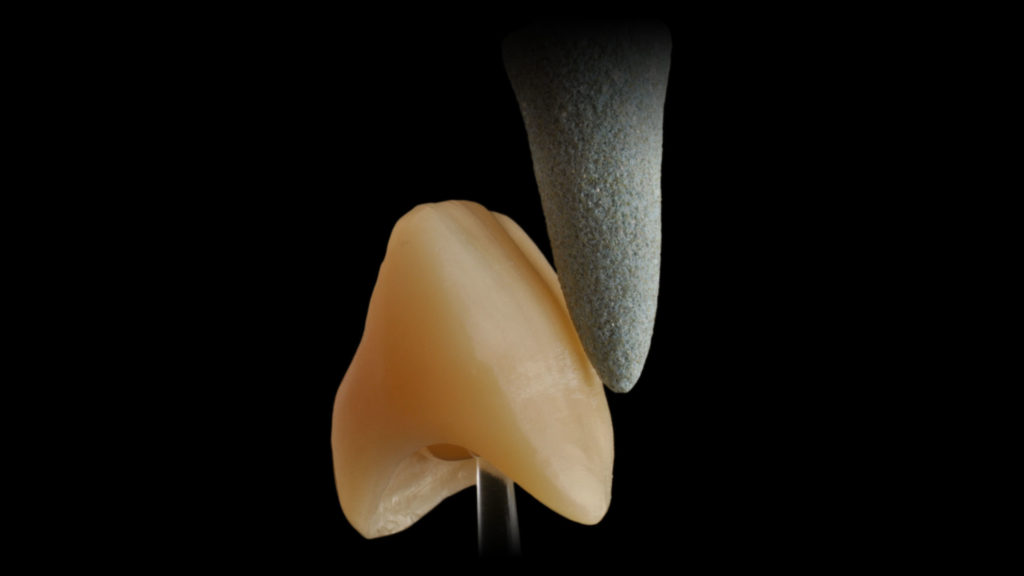

Der Schlüssel für einen neuen ästhetischen Ansatz in der Vollkeramik ist das innovative mehrschichtige Katana Zirkonoxid, ein mehrschichtiges transluzentes Zirkonoxid, das nun in den kompletten Vita Farben und in drei Modifikationen erhältlich ist. Je nach Indikation und je nachdem, welche Balance aus Festigkeit und Transluzenz gewünscht oder gefordert ist, stehen also folgende Varianten zur Verfügung:

- Katana Zirconia HTML – Hochtransluzentes (HT) Multilayer (ML) Zirkonoxid mit einer Festigkeit von 1200 MPa

- Katana Zirconia STML – Supertransluzentes (ST) Multilayer (ML) Zirkonoxid mit einer Festigkeit von 750 MPa

- Katana Zirconia UTML – Ultratransluzente (UT) Multilayer (ML) Zirkonoxid mit einer Festigkeit von 550 MP (Abb. 4).

Selbst bei komplexeren Restaurationen sind sehr dünne Verblendkeramikschichten von 0,3 bis 0,8 mm (Abb. 41) keine Utopie mehr. Mit einem entsprechenden Zirkonoxid als tragendes Gerüstmaterial kann man so dem Anspruch an langzeitstabilen Zahnersatz trotz geringer Verblendkeramikschichtstärke seht gut nachkommen.

Bei Fällen von mittlerer Komplexität erlauben es uns Cut-backs von 0,3 bis 0,0 mm (Abb. 42) mit sehr dünnen Keramikschichten (Microlayering) im sichtbaren Bereich ein ästhetisch sehr gutes Ergebnis zu generieren.

Für den Fall, dass eine Situation mit geringer Komplexität vorliegt, stehen uns auch hier vollkeramische Materialkonzepte zur Verfügung, die ohne ein Cut-back des Zirkonoxids auskommen (Abb. 43), und bei denen sich mit Ultramikro-Schichttechniken sehr gute Ergebnisse erzielen lassen.